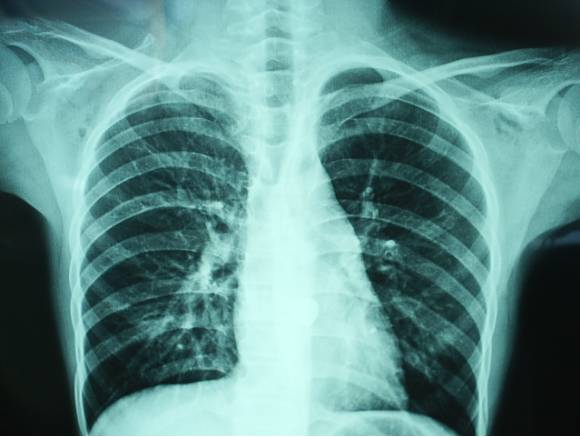

胸片

X线胸片,通俗地被称为“拍片”,也列为常规体检的检查项目之一。

胸片经常用于检查胸廓(包括肋骨,胸椎,软组织等),胸腔,肺组织,纵隔,心脏等等的疾病。如肺炎,肿瘤,骨折,气胸,肺心病,心脏病。

1、胸片能够观察肺部、胸膜、纵隔及心脏、大血管病变、四肢骨骼骨折和关节脱位。 |